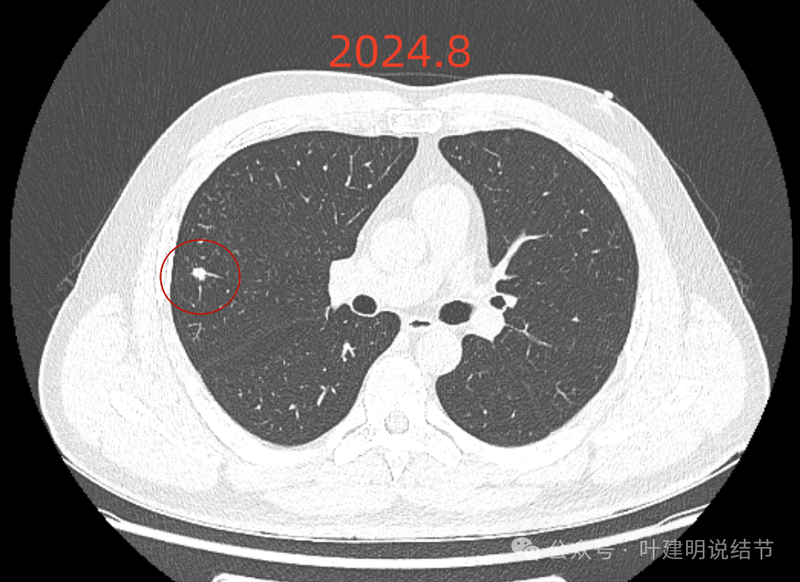

我们先来看2024年8月时的影像:

右上叶实性结节,边缘不光滑,有血管征,内部密度稍不均,整体轮廓较为清楚。